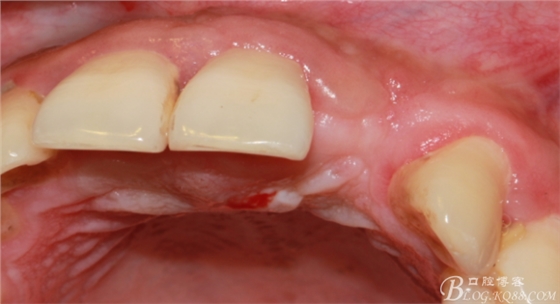

于是我果斷告知患者,手術(shù)失敗了,不能拖延,如不及時(shí)處理,炎癥繼續(xù)發(fā)展會(huì)很快波及鄰牙牙槽骨。患者接受我的建議。切開翻瓣,骨粉及生物膜消失了,骨吸收嚴(yán)重,幸運(yùn)的是,因?yàn)樘幚砑皶r(shí),鄰牙骨支持依然存在。